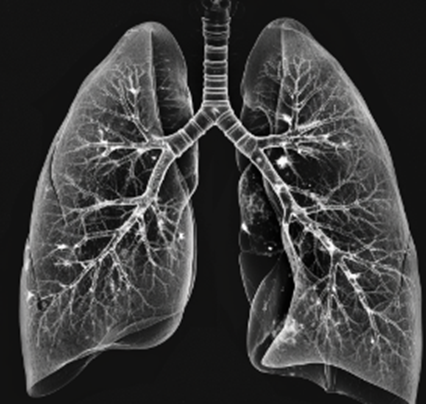

폐결절과 폐암

폐결절의 크기는 중요한 요인 중 하나입니다. 결절의 크기가 클수록 악성일 가능성이 높아지기 때문에, 정기적인 검진을 통해 크기를 모니터링하는 것이 중요합니다.

또한, 결절의 형태도 중요합니다. 불규칙한 형태의 결절은 악성일 가능성이 높기 때문에, CT 스캔 등을 통해 정확한 형태를 확인하는 것이 필요합니다.

성장 속도 역시 중요한 지표입니다. 빠르게 성장하는 결절은 악성일 가능성이 높기 때문에, 주기적인 검사를 통해 성장 속도를 확인하는 것이 중요합니다.

흡연력 또한 중요한 요인입니다. 흡연자는 비흡연자에 비해 폐결절이 폐암으로 발전할 가능성이 높습니다. 따라서 흡연자들은 특히 정기적인 검진을 통해 폐 상태를 확인하는 것이 중요합니다.